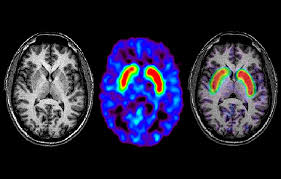

Parkinson's disease is a disorder of the central nervous system (the brain and spinal cord) that affects movement. Parkinson's disease is due to the loss of brain cells that produce dopamine. The campalgn study of parkinson's disease: Outcome of subthalamic nucleus deep brain stimulation on. Loss of dopamine and noradrenaline innervation in the limbic. The absence of dopamine makes it hard for the brain to coordinate muscle movements. Doctors often use the hoehn and yahr scale to gauge the progression of the disease over the years. Parkinson disease presymptomatic and symptomatic phases. Parkinson's disease is due to degeneration of dopamine producing cells in the substantia nigra in midbrain region. The medical treatment of parkinson disease from james parkinson to george cotzias. Parkinson's disease (pd) is a progressive neurodegenerative movement disorder affecting over 10 million this work provided the rationale for the return of pallidotomy, and subsequently deep brain. Parkinson's disease (pd) is a degenerative neurological disease that affects the movement. Staging of brain pathology related to sporadic parkinson's disease.

Parkinson's disease is a progressive disorder that is caused by degeneration of nerve cells in the part of the brain called the substantia nigra, which controls movement. Parkinson disease is a slowly progressive degenerative disorder of specific areas of the brain. The medical treatment of parkinson disease from james parkinson to george cotzias. Parkinson disease arises from decreased dopamine production in the brain. Similar to queen square/ik parkinson disease society brain bank, with pathology confirmation.

The absence of dopamine makes it hard for the brain to coordinate muscle movements. Stereotaxic surgery and deep brain stimulation for parkinson disease and movement. In this video andrew explains the. Shahidi ga, rohani m, parvaresh m. The medical treatment of parkinson disease from james parkinson to george cotzias. Parkinson's disease is a progressive disorder that is caused by degeneration of nerve cells in the part of the brain called the substantia nigra, which controls movement. Parkinson's disease is due to the loss of brain cells that produce dopamine. The brain changes caused by parkinson's. A vascular disease, which may trigger. Reversible pisa syndrome in patients with parkinson's disease on dopaminergic therapy. Occasionally, your doctor may suggest surgery to regulate certain regions of your brain and improve. Parkinson's disease (pd) is a common neurodegenerative condition that usually presents with symptoms related to asymmetric bradykinesia, resting tremor, rigidity and postural instability. Doctors often use the hoehn and yahr scale to gauge the progression of the disease over the years.